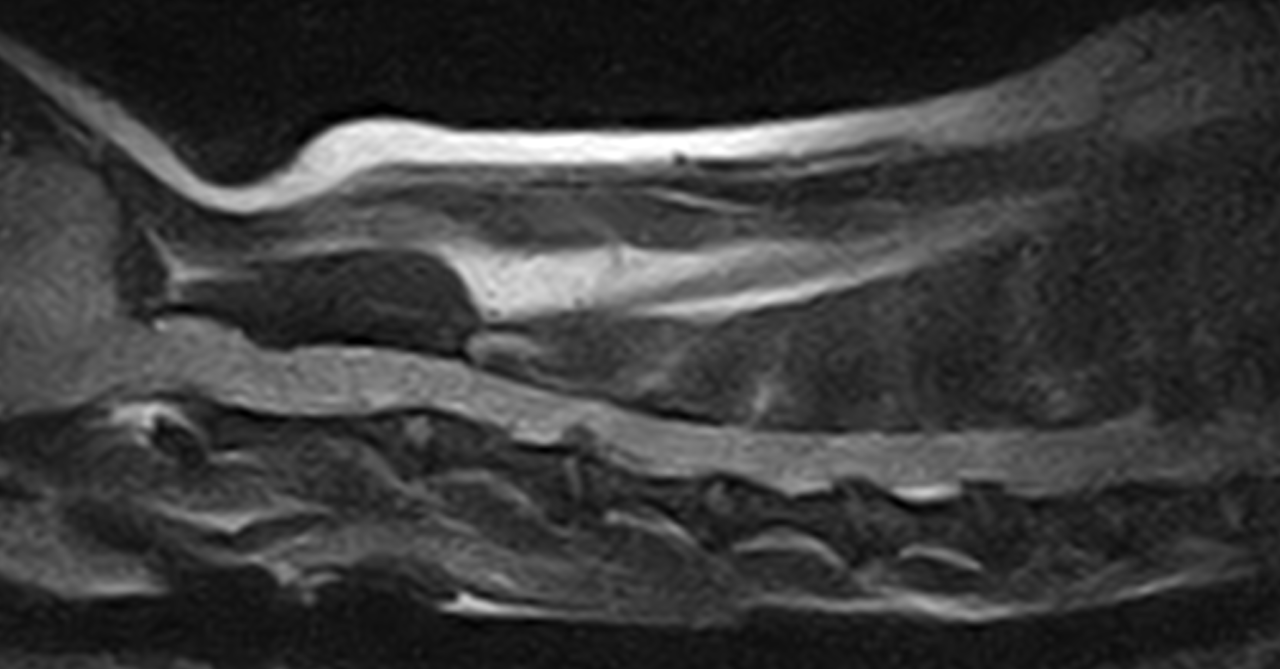

Ventral Slot チワワちゃんの頸部椎間板ヘルニアC3~C4 Ventral Slotで脊髄減圧術。しばらくは安静が必要です。 症例カテゴリー 放射線治療整形外科軟部組織外科脳神経外科内科腫瘍外科救急・集中治療リハビリテーション科腫瘍内科内視鏡科脳神経科呼吸器外科中医・漢方猫の腎移植循環器科